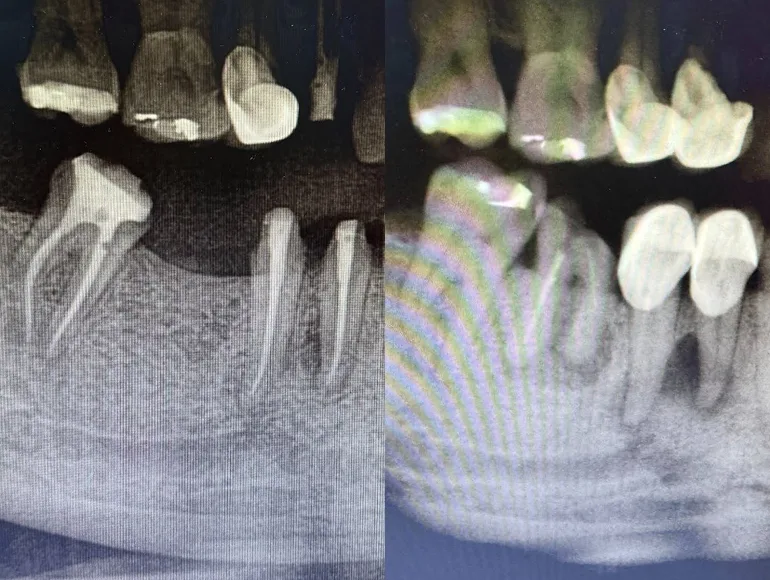

Extreme Curved Roots

Case by Dr. Taha Azimaie: Rootcanal treatment in extreme curved roots is technique sensitive procedure and require skills and right equipments.